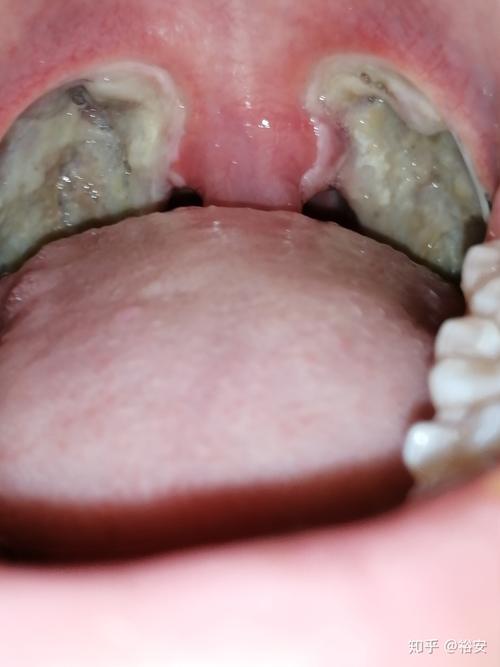

扁桃体切除手术后腭垂与创面粘连!

割完扁桃体就发生了这种情况,粘连,根本看不到小舌头

小舌头跟扁桃体粘连图

扁桃体粘连图片